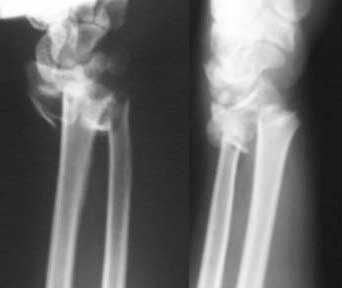

Thank you all for the encouraging participation in discussing this case. This is what I have done: I had doubt on the carpal bone involvement and a 3DCT scanwas done and this ruled it out. Patient was immediately taken up and a closed manipulation with ligamentotaxis using JESS/ UMEX (I really do not know the difference between the two, advantages / disadvantages except that UMEX is slightly coslty) under image intensifier was done. The picture is attched for your viewing. Subsequently I have added two diagonal connecting rods between the two sides to add stability. Lots and lots of elevation, mobilisation of fingers, elbow and shoulder etc done. The numbness in the median nerve area has improved significantly. This week it will be three weeks and the swelling is settled to a large extent. I am planning an elective cancellous bone grafting to the comminuted area with additional K wires as suggested by many list members and my colleagues. Would welcome further comments.